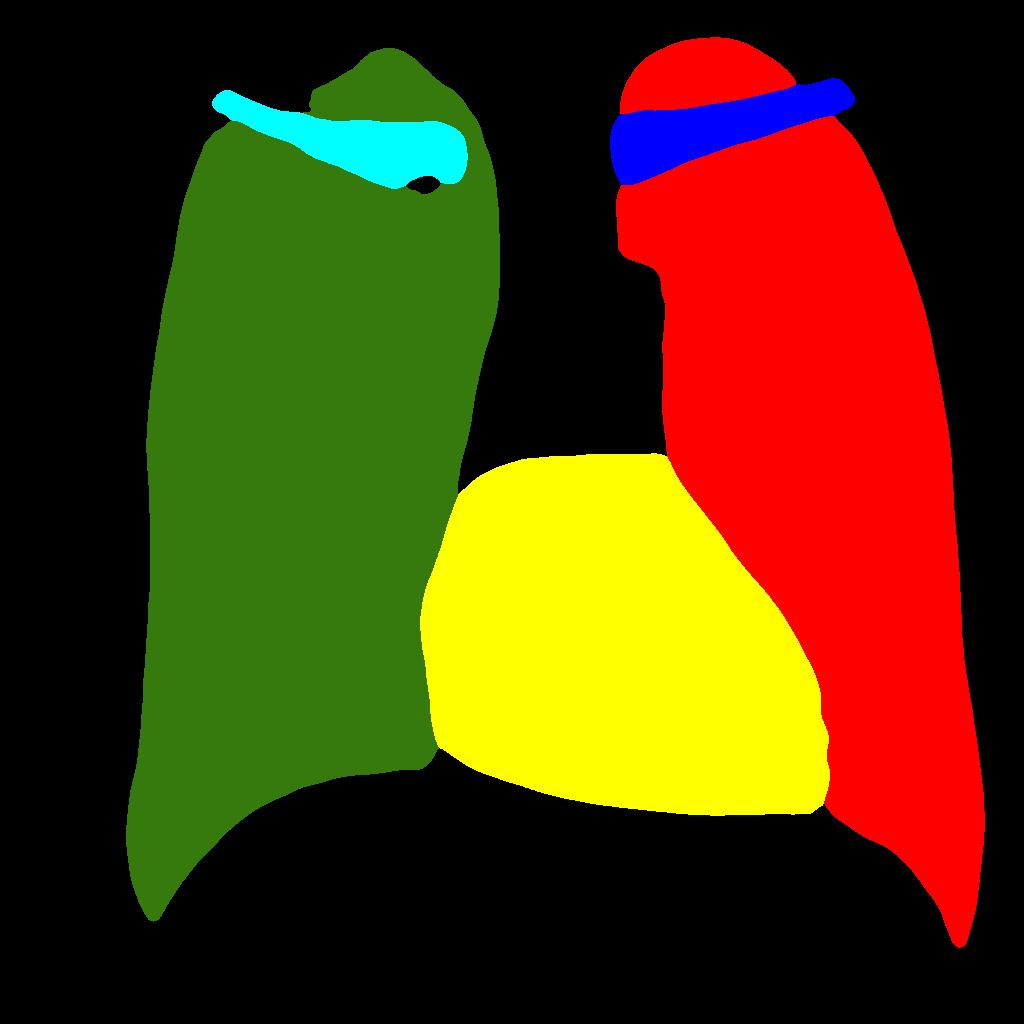

This baseline approach consists in stacking X–ray images and labels into two different channels, which are simultaneously fed into the PGGAN. Therefore, the PGGAN is trained to generate pairs composed by an X–ray image and its corresponding label (see Figure 1).

Figure 5 and Figure 6 display some examples — randomly chosen from all the generated images — of the label–maps and the corresponding chest X–ray images generated with the three methods described in Section 3, using the FULL_DATASET and the TINY_DATASET, respectively. We can observe that, with the single and two–stage methods, the images tend to be more similar to those belonging to the training set. For example, in most of the generated images there are white rectangles, which resemble those present in the training images, used to cover the names of both the patient and the hospital. Instead, the three–stage method does not produce such artifacts, suggesting that it is less prone to overfitting.